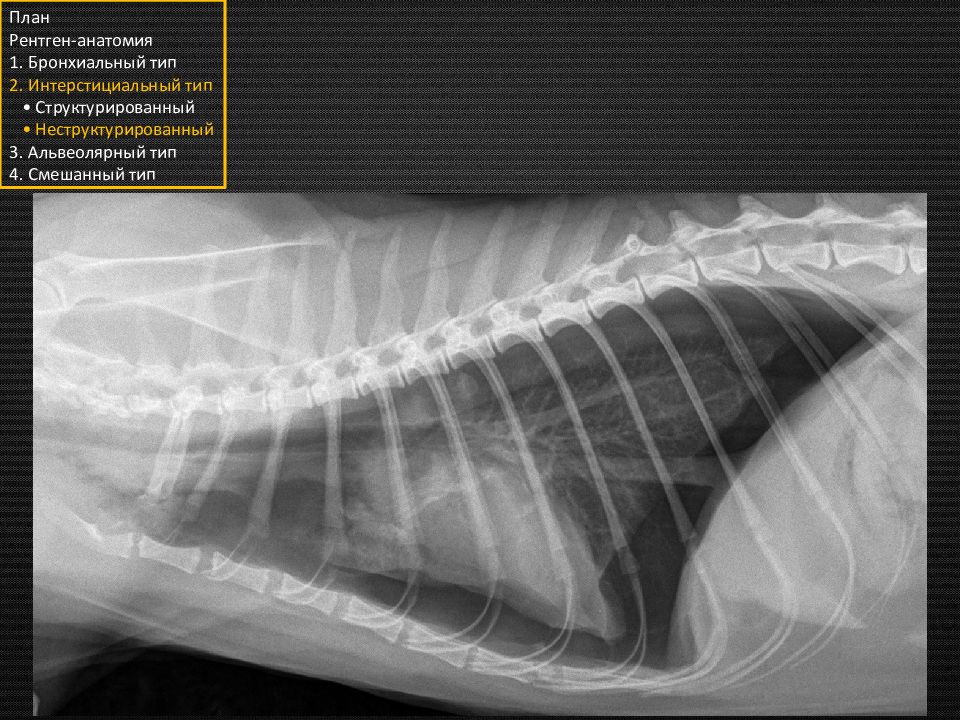

Этот подтип назван неструктурированным, так как не имеет чётких границ и неоднороден. То есть будут некоторые затемнения в лёгких, через которые мы будем видеть долевые сосуды, кости, сердечный силуэт и прочие структуры. План Рентген-анатомия 1. Бронхиальный тип 2. Интерстициальный тип • Структурированный • Неструктурированный 3. Альвеолярный тип 4. Смешанный тип «туман» «вата» «облака»